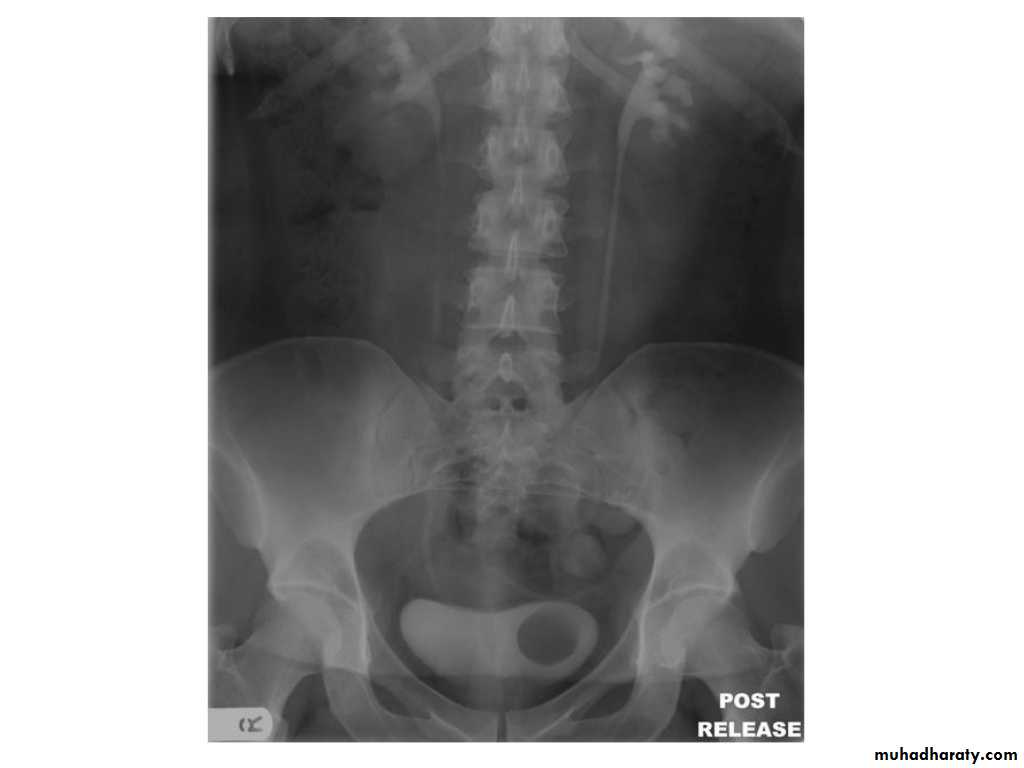

IVU shows

1. The kidneys at low position .2.Close to the spine with long axis parallel to the spine

3. Malrotation manifested by medially directed calyces.

4- The renal pelvis and ureters are anterior and lateral in position.

5- Hydronephrosis and calculi highly associated.